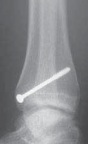

TILLAUX FRACTURES: SALTER-HARRIS TYPE III FRACTURES

1. An anterolateral approach to the ankle is used.

2. This fracture can be fixed by a distal-to-proximal, and anterior-to-posterior, compressive interfragmentary cancellous screw (

TECH FIG 3

).

3. Again, cannulated screw fixation may be used if the surgeon prefers it to the use of noncannulated screws.

22. Crossing the physis is not contraindicated in this fracture pattern because by definition the medial physis is closed and complete physeal closure is imminent.

---

A B C D

TECH FIG 3•

Tillaux fracture treatment.

A,B.

Tillaux fractures are often not seen clearly on plain radiographic views, and it is important to obtain a mortise view to see the fracture fragment that is obstructed by the fibula in standard AP views.

C,D.

CT scans often aid in fracture characterization and operative planning.

E,F.

These fractures are fixed with compressive interfragmentary cancellous screws across the fracture site, without concern for transphyseal fixation as these patients are always

E F close to skeletal maturity.